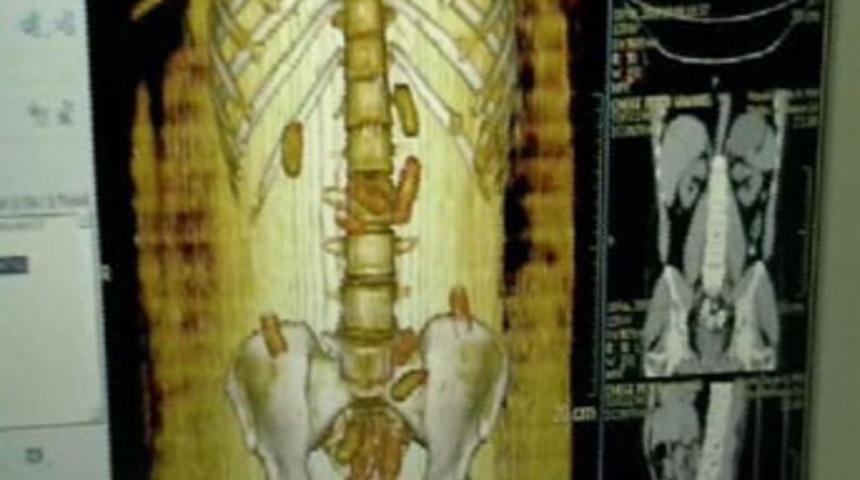

Şüphelinin ayakkabılarının içinde ve ayakkabı tabanında bir miktar daha uyuşturucu ele geçirildi. Ardından karın bölgesindeki şişlikler fark edilen şüpheli, Haseki Eğitim ve Araştırma Hastanesi'ne götürüldü. Cihaza sokularak renkli MR'ı çekilen şüphelinin midesindeki uyuşturucu kapsülleri tespit edildi. Yapılan tedavi sonucunda içinde kokain bulunan 79 adet kapsül ele geçirildi. Böylece cep, ayakkabı ve mideden olmak üzere 1 kilo 564 gram kokain bulunmuş oldu.